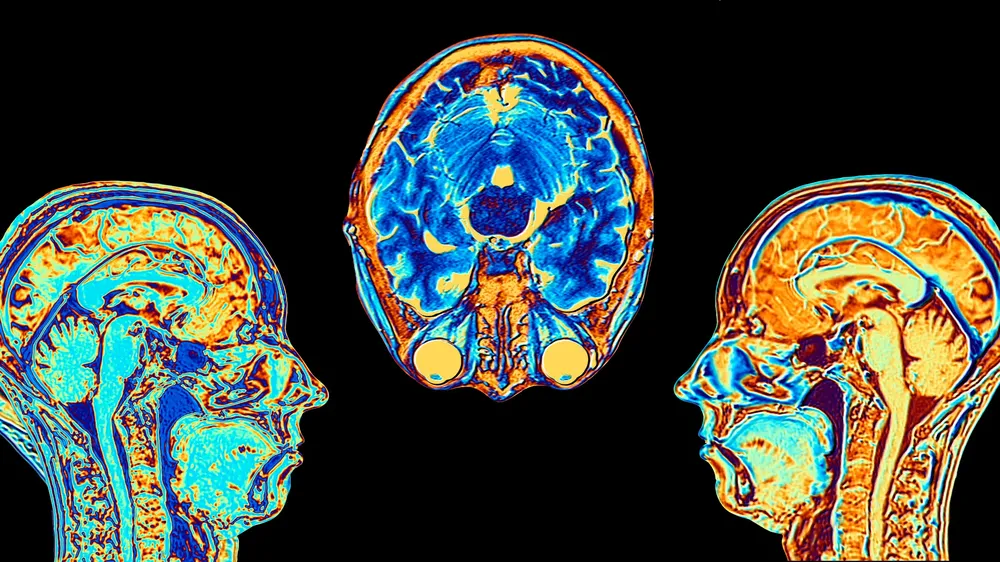

Gracias a recientes estudios científicos con resonancia magnética funcional, sabemos que los optimistas muestran mayor actividad en la corteza frontal (clave para la planificación y acción) y tienen más dopamina (el neurotransmisor de la motivación). ¡También poseen más materia gris en zonas vinculadas a la empatía y la gestión de conflictos!